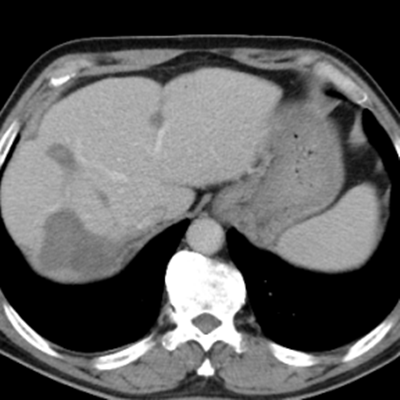

隨后,根據(jù)基因檢測結(jié)果制定了化療+靶向治療方案。經(jīng)過精準(zhǔn)治療,劉大爺?shù)牟≡畲笮⊙杆倏s小,病灶數(shù)量不斷減少,影像學(xué)評(píng)估已經(jīng)看不見之前那些小的病灶了。

治療后:未見明顯活性轉(zhuǎn)移腫瘤

經(jīng)過兩次肝臟轉(zhuǎn)移瘤射頻消融手術(shù),一次腸癌根治手術(shù)聯(lián)合腹腔轉(zhuǎn)移腫瘤切除手術(shù),劉大爺體內(nèi)的大腫瘤完全消除,僅有幾處沒有明確活性的小病灶。